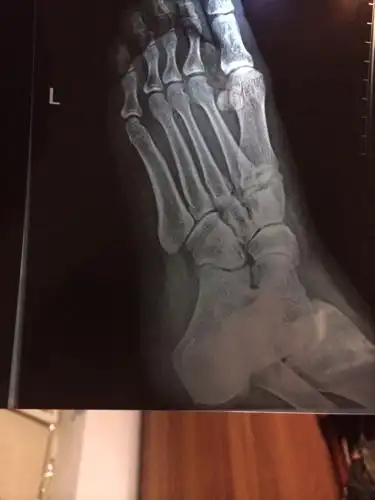

足部影像分析诊断,一文搞定!

一例极易漏诊的足部损伤

这张脚部ct能看出什么结果?

x线及ct - 影像医学和核医学讨论版 -丁香园论坛

拍片子判断左足第一四跖骨基底部骨皮质连续性差,ct报告第四跖骨基